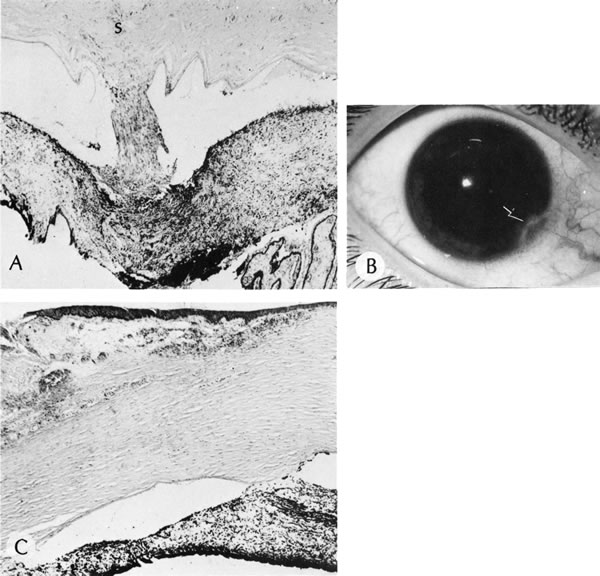

There are multiple nonspecific types of congenital corneal opacities. Although arrested embryogenesis or intrauterine inflammation may cause the entity, the opacities have the same clinical characteristics as acquired changes following trauma. In order of progressive severity, the degree of opacification is called a facet when only Bowman's membrane is involved; a nebula when the area of opacification is diffuse, cloudlike, and has indistinct borders; a macula when the area is dense and has a circumscribed border; and a leukoma when the cornea is opaque. Adherent leukoma is a subgroup in which a portion of iris is fused to the posterior surface of the opaque corneal tissue, similar to the findings of some healed acquired corneal perforations (Fig. 2).

Fig. 2. Adherent leukoma. A. Proliferated fibrous tissue attaches the iris to the cornea through a gap in Descemet's membrane of a 3-week-old wound. An overlying scar(s) is present through the full thickness of the cornea. After organization and shrinkage of the fibrous membrane, the scar will look much like the scar of adherent leukoma seen in B. Peripheral adherent leukoma (arrow) in a 12-year-old girl who had accidental perforation of the globe by a pair of scissors 5 weeks previously. The perforation of the cornea was repaired on the day of the injury. Sympathetic uveitis developed 2 days before the photograph was taken. C. The peripheral iris is adherent to the corneal stroma through a gap in Descemet's membrane. The overlying stroma is scarred. (Courtesy of SEI Photoarchives.)

Histopathologic findings include absence of Descemet's membrane, corneal endothelium, and usually Bowman's membrane, as well as thinning of corneal stroma. The defects in Descemet's membrane, although usually single and central, may be multiple and isolated to the periphery or may be limited to an area of adhesion of iris.56 Descemet's membrane has been found to have embryonal ultrastructural characteristics combined with attenuated endothelium.57 The corneal stromal lamella are more irregular and closely packed when compared with normal. Immunohistochemical markers indicate that a normal complement of collagens type I, III, IV, V, and VI occurs in Peters' anomaly; however, an increased concentration may occur of the adhesive protein fibronectin, which is known to play a role in the embryologic development of the cornea.58–60